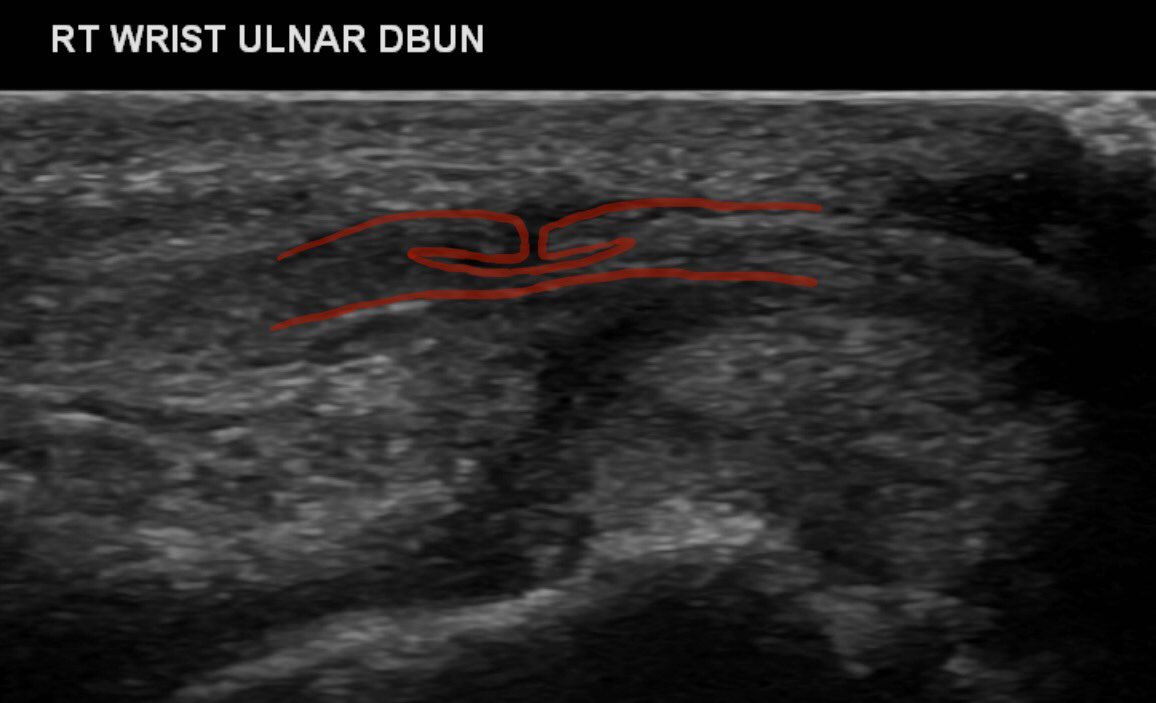

Glass injury in a RHD joiner presented 1/52 following injury with painful parasthesia in distribution of dorsal branch of the ulna nerve. Unbelievable diagnostic accuracy from @YorkshireRad with nerve found to have longitudinal split on exploration #FOAMed #FOAMrad #orthotwitter